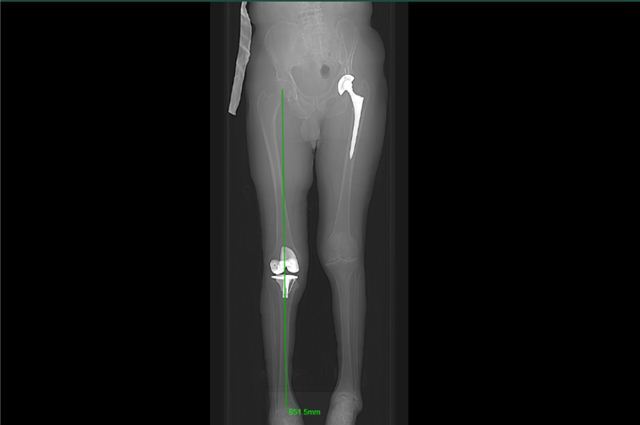

术后病人非常满意,以前他畸形的腿变直了,也可以正常弯曲了,可以像正常人一样行走,他还在期待另一侧的手术。

术后X片

转眼之间,阿坝县人民医院的帮扶支援快结束了。这一年,在医院的支持下,带领我的徒弟开展一百余台手术,包含髋关节置换、膝关节置换和各种骨折内固定手术等。新开展了加长柄髋关节置换治疗老年粗隆间骨折、间隙平衡技术在膝关节置换中的应用和抗生素骨水泥治疗慢性骨髓炎等新技术。